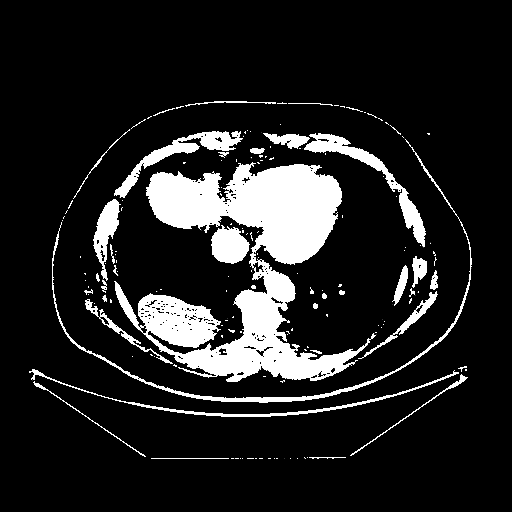

Generated VENOUS CT scan (A→B translation)

Full window (WL 1023.5, WW 4095 β†’ Low βˆ’1024, High +3071)

Actual HU range: [-1024.0, 3071.0]